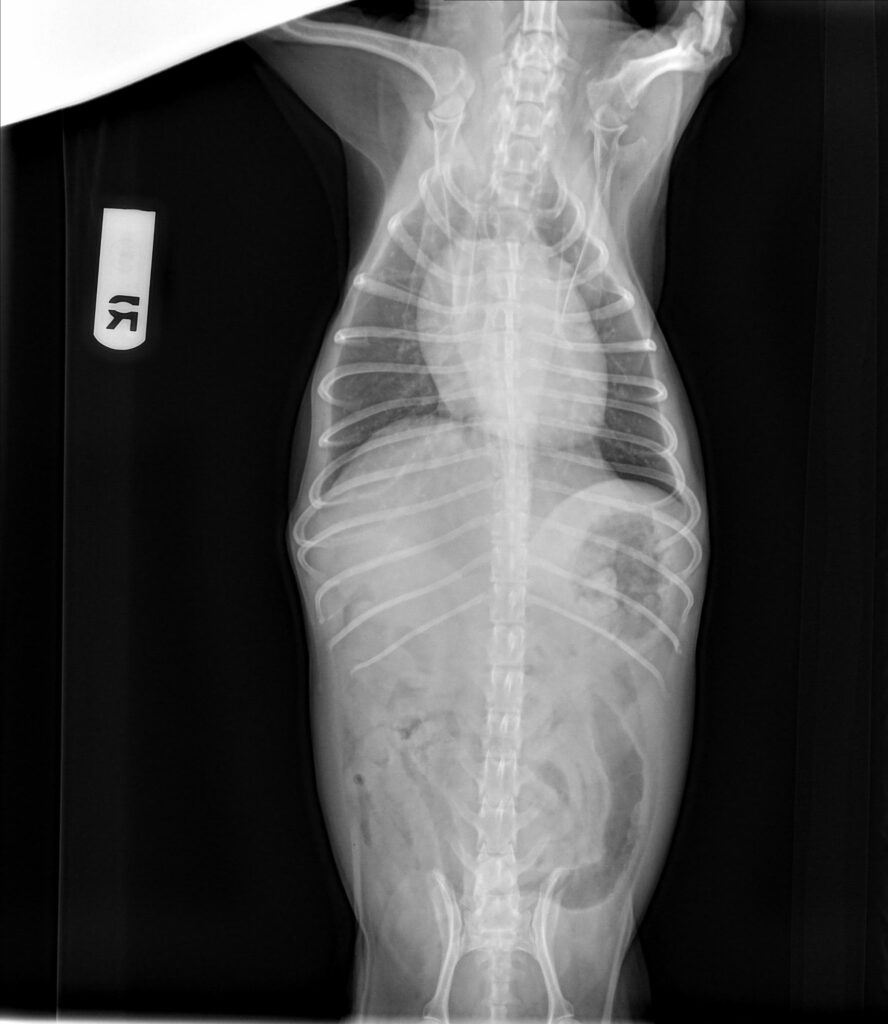

The patient presented for vomiting, labored breathing and a low appetite. The patient has a history of chronic valvular disease (previous echo read by Sonopath). He is currently managed on pimobendan, enalapril and furosemide. Radiographs showed cardiomegaly with possible mild pulmonary edema in the perihilar region.

Radiographs taken at the referring veterinary hospital: